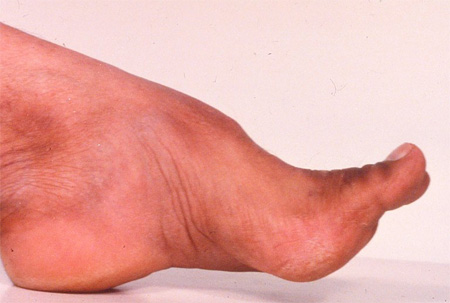

Pes cavus დეფორმაცია ფრიდრიხის ატაქსიის მქონე პაციენტებში

ექიმი ს.ჰ. საბრამონის კოლექციიდან; გამოყენებულია მფლობელის ნებართვით